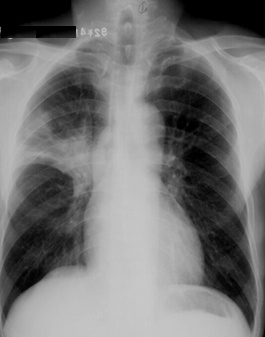

斑片狀陰影位于雙肺尖,根據(jù)公式診斷浸潤性肺結(jié)核